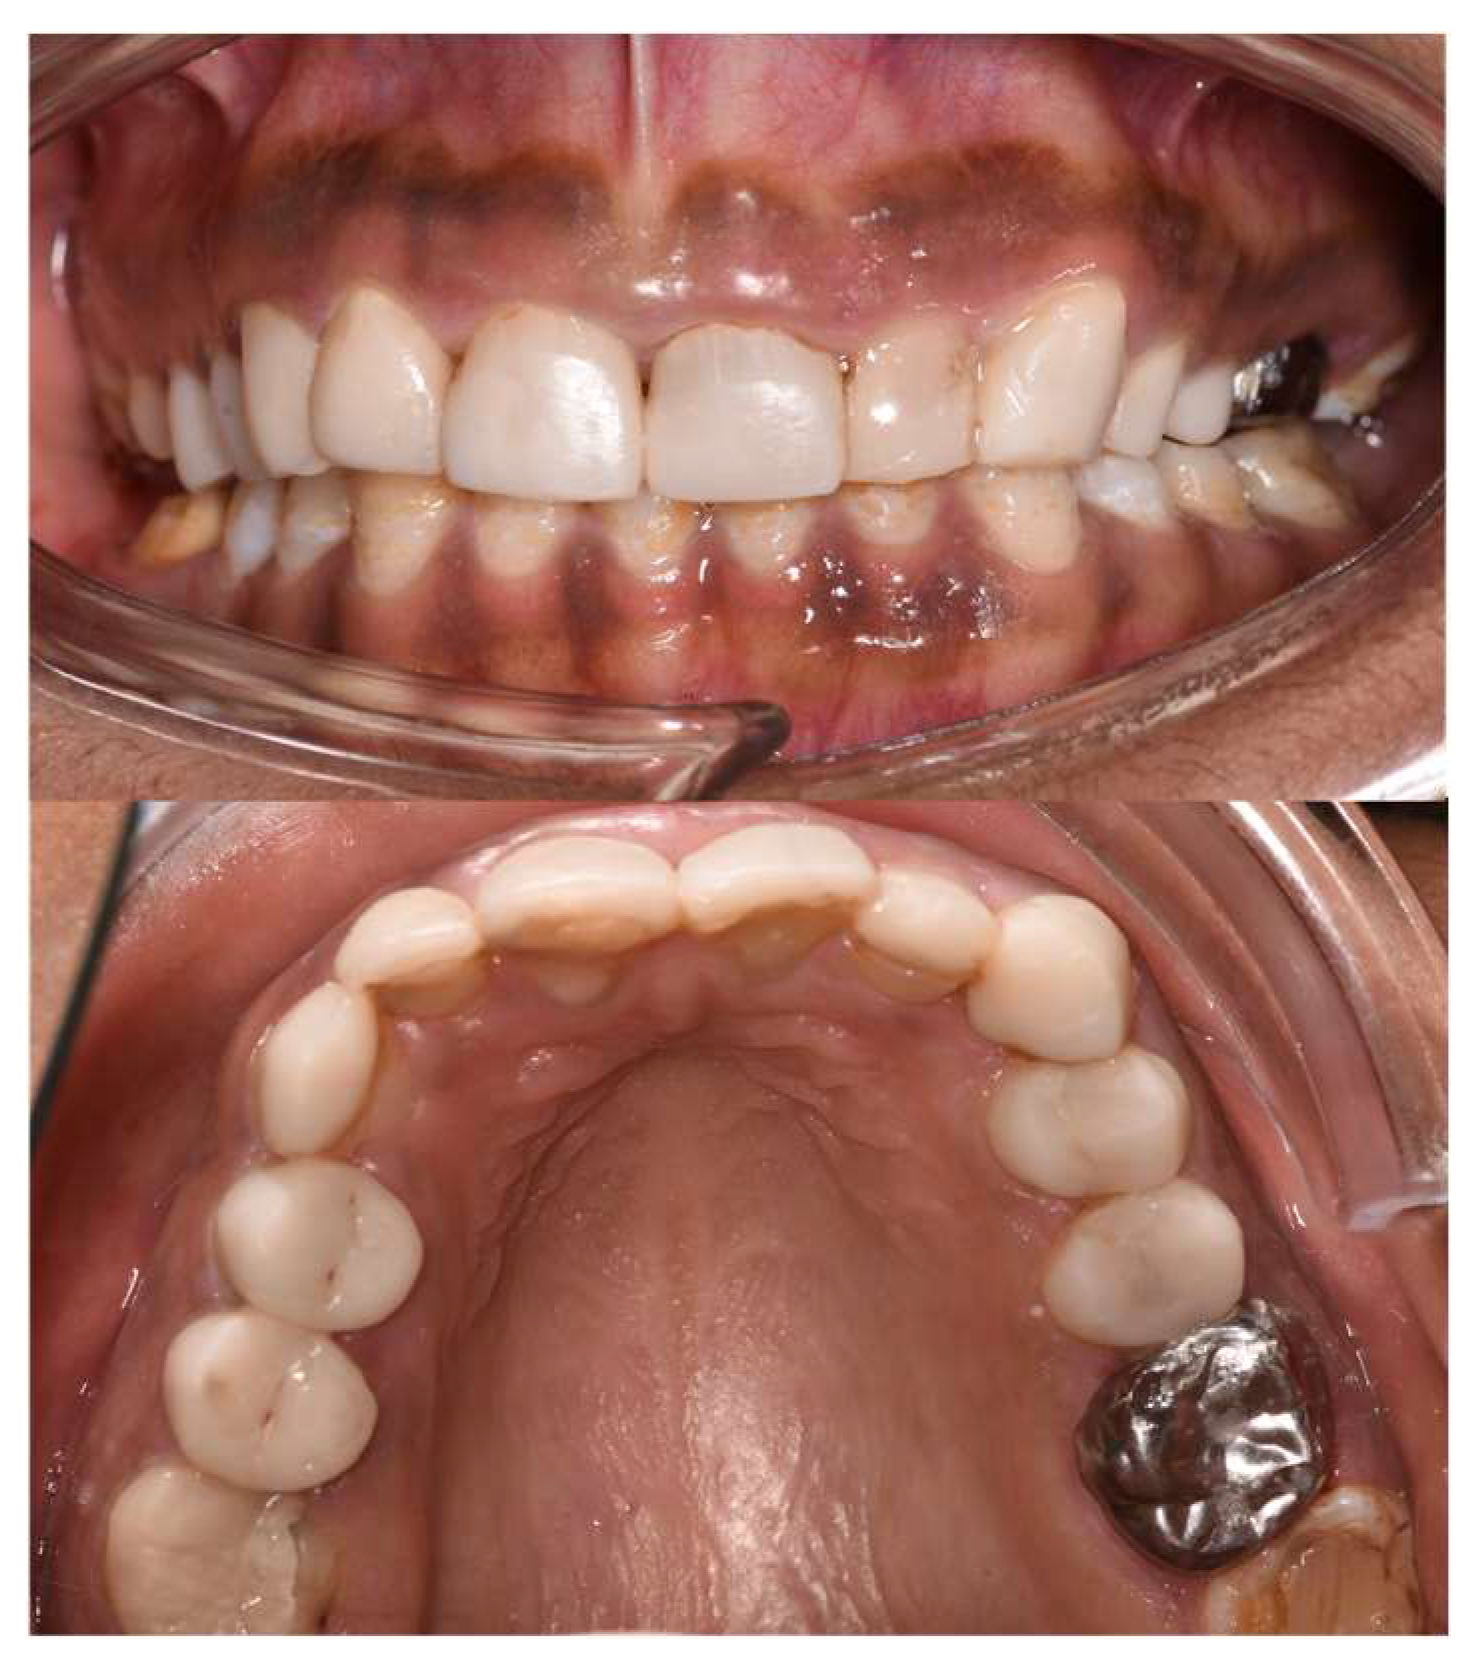

2.2. Clinical Examination

2.11. Follow-Ups

2.11.1. At 15 Days

2.11.2. At 3 Months

2.11.3. At 8 Months